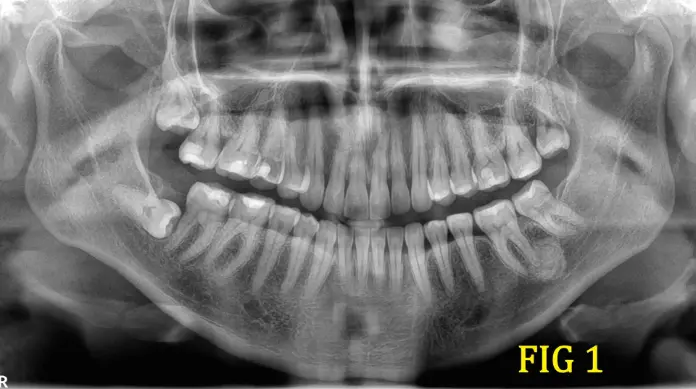

Se presenta el caso de un paciente femenino asintomático, de 37 años de edad que acude al centro de imágenes para la realización de una radiografía panorámica (IMG 1), indicado para extracción de 3eros molares. A la hora de la realización del estudio se puede observar una lesión radiopaca en zona de pieza radicular 36.

Días posteriores a la realización del primer estudio la paciente vuelve con indicación de la misma odontóloga de una tomografía cone beam enfocada en la zona de la lesión mencionada anteriormente(IMG 2), donde podemos observar con más claridad en el corte sagital, la lesión hiperdensa con bordes definidos que posee un halo periférico hipodenso, que se fusiona con la raíz dental de la pieza 36 (IMG 3), también se logra observar como el crecimiento de este tumor empieza a empujar la cortical del hueso maxilar (IMG 4).los signos que se presentan hacen pensar que estamos frente a un Cementoblastoma, el diagnóstico se confirma histológicamente tras la exodoncia o biopsia.

El cementoblastoma es un tumor odontogénico benigno y poco frecuente que se origina a partir de los cementoblastos, células encargadas de formar el cemento radicular. Se presenta con mayor frecuencia en pacientes jóvenes, afectando típicamente molares o premolares mandibulares. Radiológicamente, se manifiesta como una lesión radiopaca bien delimitada que se encuentra fusionada a la raíz del diente afectado, con un halo radiolúcido periférico característico.